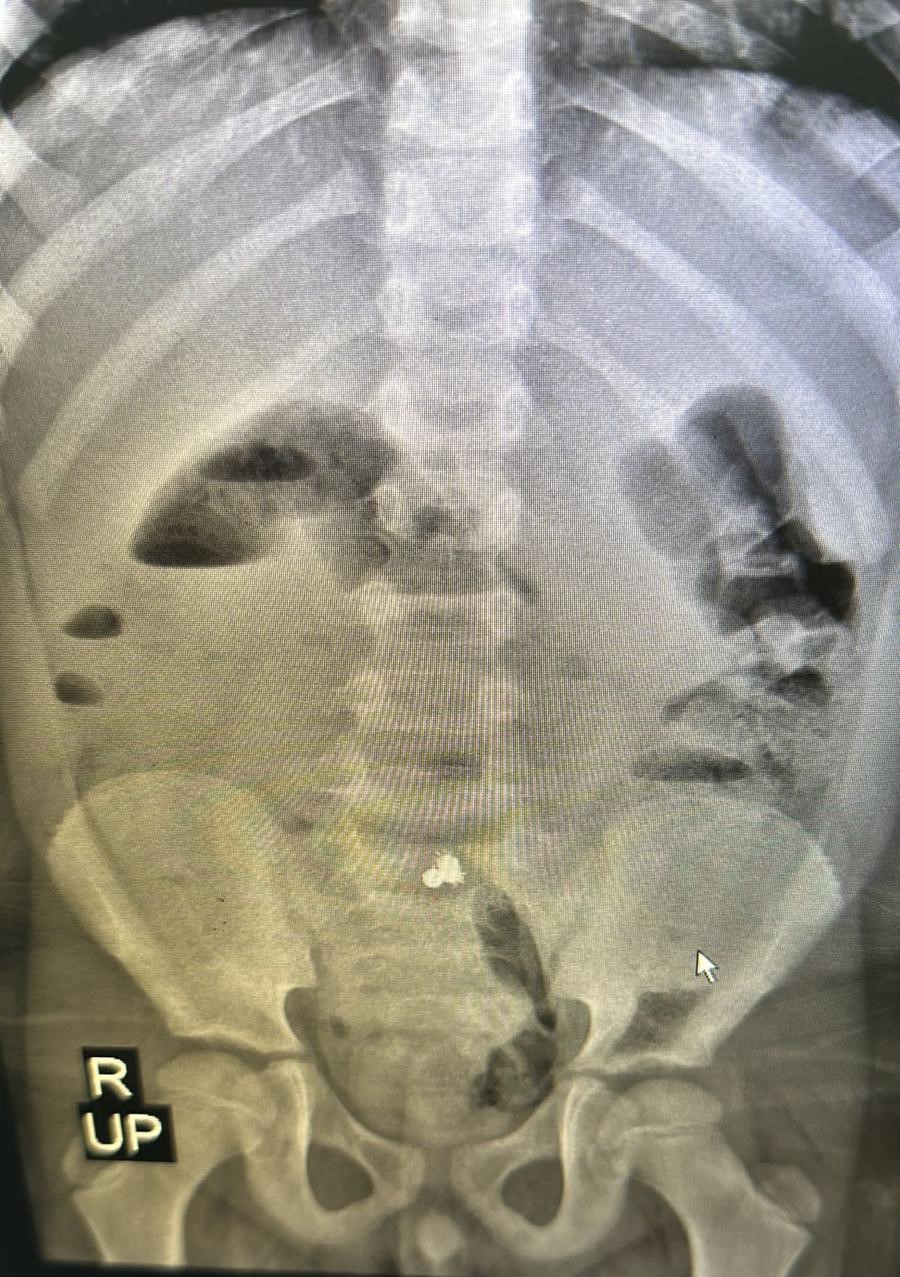

Rize’de 7 yaşındaki Miraç Kalay, 11 Nisan Salı günü okulda karın ağrısı şikâyeti üzerine öğretmenleri tarafından babası Orhan Kalay’a (37) haber verildi. Baba oğlunu okuldan aldıktan sonra aile hekimine başvurdu. Aile hekimi yaşanabilecek en ufak sıkıntıda hastaneye başvurmaları gerektiğini aileye belirtti. Daha sonrasında eve giden 7 yaşındaki Miraç, art arda kusmaya başlayınca Rize Devlet Hastanesi acil servis bölümünde tedavi altına alındı. Acil bölümünde yapılan müdahalelerin ardından Miraç’ın midesi için film çekilmek istendi. Çekilen filmin ardından MR’da küçük Miraç’ın mıknatıslı demir bilyeler yuttuğu tespit edildi. Miraç daha sonrasında Recep Tayyip Erdoğan Üniversitesi Eğitim ve Araştırma Hastanesine nakil edildi. 12 Nisan Çarşamba günü saat 08.20 sıralarında ameliyata giren Miraç yaklaşık 1 buçuk saatlik başarılı ameliyatın ardından sağlığına kavuşarak tedavisine devam edilmek üzere serviste gözlem altına alındı. Miraç şimdi ise hastaneden taburcu olmayı bekliyor. Küçük Miraç’ın ameliyatını yapan RTEÜ Eğitim ve Araştırma Hastanesi Çocuk Cerrahisi uzmanı Halil İbrahim Çakmak, ailelerin çocuklarını küçük oyuncaklardan korumaları gerektiğini söyledi.

Evlerde çocukların yutabileceği küçük cisimlerin bulundurulmaması gerektiğini ifade eden Çocuk Cerrahisi uzmanı Halil İbrahim Çakmak ise “Hastamız 7 yaşında erkek bir hasta. Karın ağrısı şikayetiyle acil servise başvuruyor. Hastamızın acilde çekilen filminde manyetik özelliği olan metalik bir cisim yuttuğu görülüyor. Yapılan incelemede bağırsaklarda delinme olduğu obje yuttuğu görüldü. Acil şekilde ameliyata alındı. Ameliyatta yuttuğu objenin manyetik özelliği olan 3 obje olduğu ve bağırsağı 3 yerden deldiği gözüktü. Şu anda sağlığına kavuşturuldu. Bu tip oyuncakları, objeleri evde bulundurmamak gerek. Çünkü bağırsak delinmesi hayati tehlike oluşturan bir durum. Bu bakımdan evimizde çocukların yutabileceği boyutta oyuncakları bulundurmayalım” şeklinde konuştu.